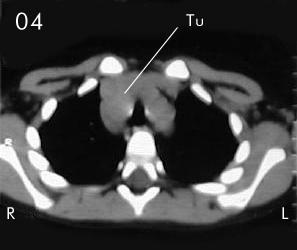

Tomografía torácica

Estudio Tomográfico tórax completo: En detalles los cortes progresivos desde el manubrio esternal hasta 2 cm sub carinal traqueal. (vistas desde el abdomen), (R) = derecho , (L) = Izquierdo; no se apreciaron procesos en pleura ni parenquima pulmonar.

En Mediastino antero superior:

Corte 02 y Corte 03: Se aprecia imagen de densidad de partes blandas en correlación con probable timo hiperplásico y/o timoma, extendiendose lateralmente a la derecha de la traquea con compresión y deformidad de la luz traqueal.

Corte 04: observe la extensión a ambos lados de la traquea a su nivel supra carinal y su compresión en el eje transverso de sus paredes.